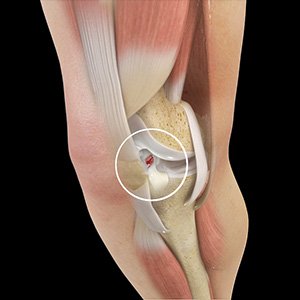

Picture of ACL Tears

ACL Tears

The anterior cruciate ligament (ACL) is one of the major ligaments of the knee. It is located in the middle of the knee and runs from the femur (thighbone) to the tibia (shinbone). The ACL prevents the tibia from sliding out in front of the femur. Together with the posterior cruciate ligament (PCL), it provides rotational stability to the knee.